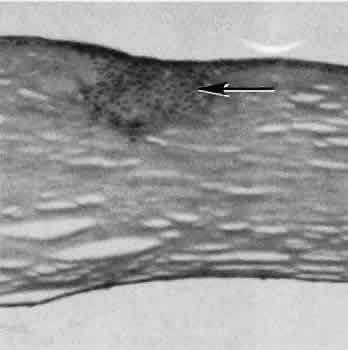

Cyclocryotherapy, cyclodiathermy (Fig. 20), and therapeutic ultrasonography apply energy directly to the pars plicata and cause lysis of the ciliary muscle and occlusion of the vascular supply, leading to extensive necrosis and scarring. Pressure lowering is accomplished by a reduction of aqueous production. Heat applied to the sclera may cause necrosis and localized scleral thinning. Cold applied to the sclera, unless extreme, does not cause any clinical or histologic changes.

Fig. 20. Cyclodiathermy treatment of the ciliary body to control glaucoma. A. Gross photograph illustrates extensive areas of depigmentation mainly in the region of the pars plana (arrows) rather than the pars plicata. B. Light micrograph of the region of the pars plana illustrates an extensive area of tissue degeneration of the pars plana (between arrows) in the late postoperative course. C. Light micrograph of the destructive effects of cyclocryotherapy also in the region of the pars plana and pars plicata. The ciliary epithelium in the early postoperative period is necrotic and cystic. (Hematoxin-eosin stain; A, × 8; B, × 16.)